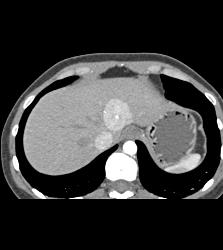

Focal Nodular Hyperplasia (FNH)